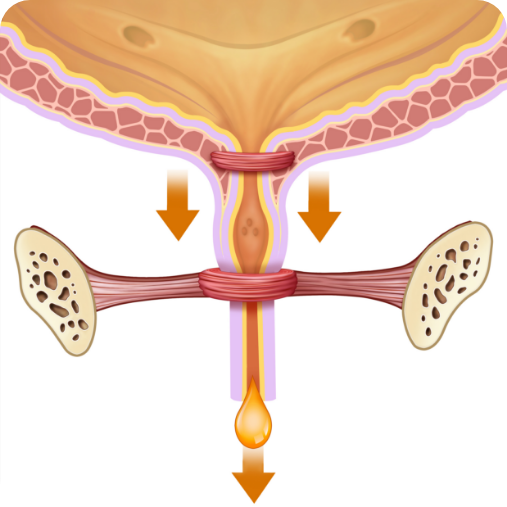

PŘED kúrou:

Slabé svaly močové trubice

PO kúře:

Silné svaly močové trubice